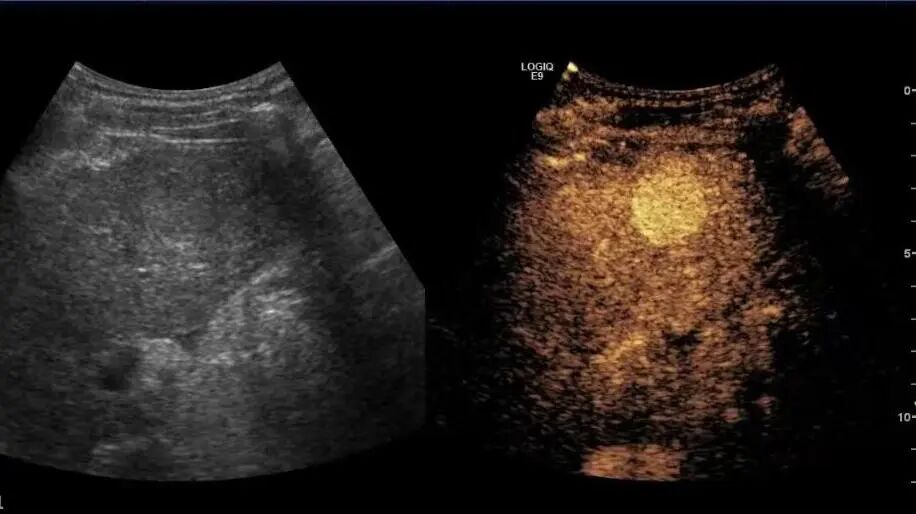

4月2日,贵州航天医院第55次晨读会由我院超声科医师敖春庆作学术交流,她以“中孕期产前超声筛查技术”为题,详细讲解了进修学习的成果,分享了科室实际开展的病例,阐述了未来的工作计划与展望,并结合典型病例图文分析等形式,强调了中孕期产前超声筛查的重要意义。 超声科专家简介 吴艳辉 中共党员,超声科学科带头人、主任,主任医师 临床擅长:从事超声诊断工作约30年,对心血管、小器官超声、超声引导下介入等具有丰富的临床经验。 骆科美 中共党员,超声科副主任医师 临床擅长:从事超声诊断工作33年,对胎儿心脏及颅脑、妇产超声、盆底超声等诊断具有丰富的临床经验。 胡大海 超声科副主任医师 临床擅长:从事超声工作17年,对心血管、外周血管、浅表器官超声诊断等具有丰富的临床经验。 刘 敏 超声科副主任医师 临床擅长:从事超声诊断工作20余年,对妇产科超声、心脏血管超声诊断具有丰富的临床经验。 敖春庆 超声科主治医师 临床擅长:对腹部、泌尿、妇科等超声诊断具有丰富的临床经验。 超声科简介 基本情况 贵州航天医院超声科配备多种超声检查设备(飞利浦彩超(IU-22、IU-Elite、HD11、Q5、Q7),迈瑞超声I9、DC-6、DC-8、GE-E8及床旁机,彩色超声诊断仪等),设有心血管诊室、妇产科诊室、腹部诊室、浅表小器官等检查室。 专科特色 四肢血管超声检查、双胎产前筛查及超声监护、超声造影检查技术、介入超声临床应用、经颅脑实质超声辅助筛查诊断帕金森病、女性性早熟超声诊断、盆底超声检查等。 NT超声检查 超声介入引导 肝脏超声造影 甲状腺造影 颅脑超声帕金森辅助检查 乳腺超声造影 上肢动静脉造瘘超声检查 双胎超声筛查 下肢血管超声检查 右心造影 诊疗范围 科室业务覆盖腹部、泌尿、妇科、产科(常规、NT筛查、III级筛查超声检查及高危妊娠监护)、成人心脏、外周血管、浅表器官(包含甲状腺、乳腺、阴囊、眼睛等)、颅脑(小儿颅脑、成人颅脑)、小儿肺超、造影、盆底、腹直肌、肌骨神经等检查及各种介入引导。 end